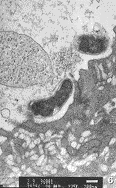

20例NIDDM病人胃粘膜微血管均有不同程度显著改变。 微血管内皮细胞均有不同程度的肿胀 , 内皮细胞的厚度是对照组内皮细胞的几倍乃至十几倍。 有1例血管内皮细胞呈气球样肿 胀, 并突向管腔, 堵塞血管腔约4/5(图1)。 胞浆形成大量指状突起伸入管腔, 有的突起 呈犬齿状, 有的互相连成网状, 与红细胞发生缠绕现象(图2)。 吞饮小泡明显增多, 大 部分吞饮小泡集中于细胞的腔面及基底面两侧。 胞浆内可见肿胀的线粒体, 有的呈空泡状 。 少见高尔基氏器及粗面内织网。 细胞连接缝隙增宽窗孔增大, 有的由于内皮细胞的肿 胀而使窗孔减少甚至消失, 有2例内皮细胞内膜部分有破损, 血小板和红细胞聚集在受损 面上。 微血管基底膜均有不同程度增厚。 有的同一病例显示部分微血管基底显著增厚, 而部分微血管基底膜增厚较轻, 提示为一种微血管的节段性基底膜增厚。 有的微血管基底 膜在内皮细胞外和周细胞周围呈层状增厚(图3)。 周细胞在胃粘膜微血管中出现较少。 周 细胞以一种不完全的包绕微血管的形式存在, 其内侧基底膜和外侧基底膜显示了同等的厚 度。 我们根据电镜下胃粘膜微血管受损程度将其分为轻、 中、 重三级。 轻度: 微血管 内皮细胞轻度肿胀, 管腔无明显狭窄, 无胞膜损害, 基底膜轻度增厚。 中度: 微血管 内皮细胞肿胀, 管腔稍变窄, 不闭锁。 基底膜增厚较明显(图4)。 重度: 微血管内皮细 胞高度肿胀, 内膜受损, 管腔狭窄, 甚至闭锁。 基底膜明显增厚。 本组20例NIDDM胃粘 膜微血管的电镜观察结果: 轻度受损2例; 中度受损16例; 重度受损2例。

图3 NIDDM 患者胃粘膜 微血管基底膜 出现层状增厚×5000